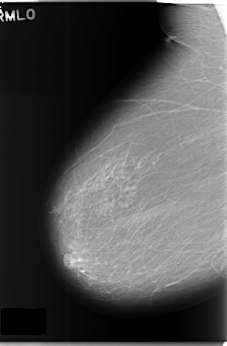

Volume: cancer_09 Case: C-0176-1

C_0176_1.RIGHT_MLO

RIGHT_MLO LINES 5880 PIXELS_PER_LINE 3848 BITS_PER_PIXEL 12 RESOLUTION 50 NON_OVERLAY